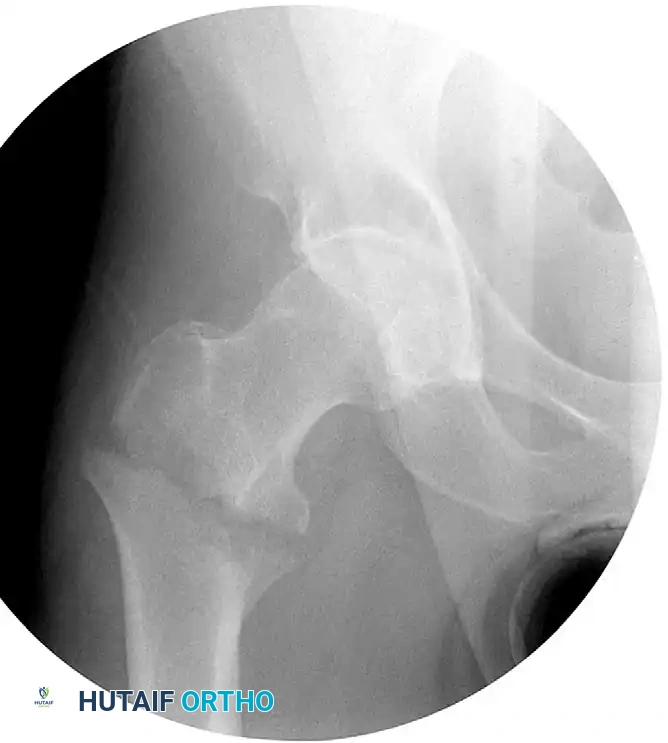

The Tip-Apex Distance (TAD)

Proper placement of the lag screw is the single most important surgeon-controlled variable in reducing the incidence of implant failure, specifically lag screw "cut-out" through the superior femoral head.

The Tip-Apex Distance (TAD), described by Baumgaertner, is calculated by summing the distance from the tip of the lag screw to the apex of the femoral head on both the AP and lateral radiographs, corrected for magnification.

* Rule of Thumb: As the TAD increases above 25 mm, the risk of biomechanical failure and cut-out increases exponentially. A center-center position inherently minimizes the TAD.

Integrity of the Lateral Wall

The lateral trochanteric wall acts as a critical buttress for the proximal fragment. When treating intertrochanteric fractures with a CHS, the integrity of this wall must be rigorously evaluated.

Clinical Pearl: In a landmark series, 22% of patients with a fractured lateral wall (A3 fractures or iatrogenic fractures in A1/A2) treated with a CHS required a reoperation within 6 months. Strikingly, 74% of these lateral wall fractures occurred intraoperatively during reaming or plate impaction.

Studies by Im and Chung identified iatrogenic lateral wall comminution as the most significant predictor of excessive fracture displacement. If iatrogenic comminution occurs, the surgeon must strongly consider augmenting the construct with a trochanteric stabilizing plate (TSP) or abandoning the CHS in favor of an intramedullary nail. Therefore, the CHS should be used with extreme caution in fractures more complex than A2.1.